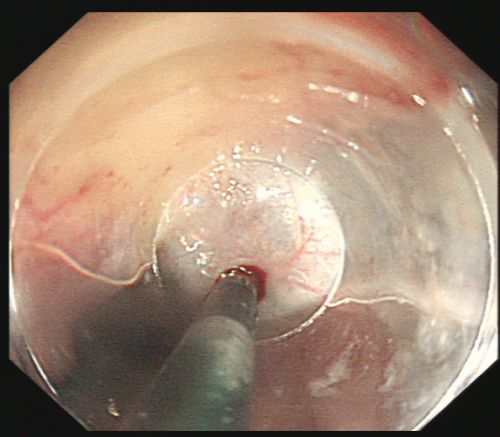

治疗后,创面无活动性出血。

由于血管压力高,手术风险大,术中发生大出血、窒息及异位栓塞的风险非常高。综合内科主任彭娅反复与家属沟通取得理解配合后,为易某实施改良后内镜下止血技术——食管曲张静脉套扎+硬化剂注射治疗。所幸手术过程顺利,术后继续予以降门脉压力、护胃、减轻腹水、维持内环境稳定等对症支持治疗。经过积极治疗,患者病情趋于稳定,已恢复饮食,精神状况好转,于215日出院。